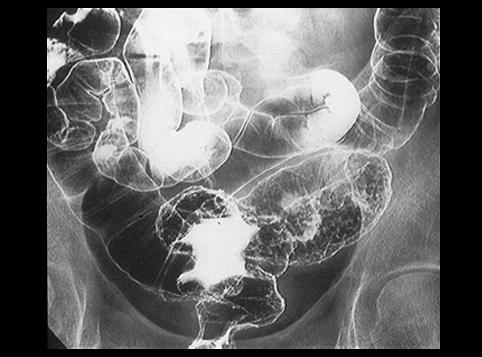

clasificación del pacienteTumor Epitelial Maligno/Adenocarcinoma

parte(separada por órganos)colon/lesión que abarca dos o más regiones del colon

método de exámenRayos X

clasificación ectoscópica de tumoresTipo 4(Tipo difusamente infiltrado)/

diámetro mayor del tumor40 -

grado de penetraciónss(a1)